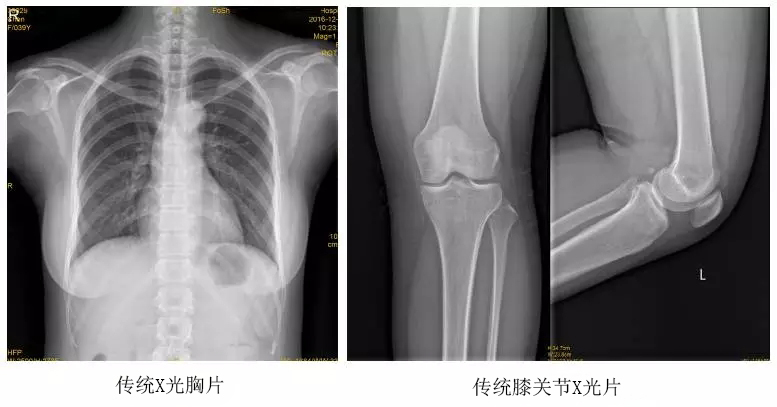

以某院所攝X光片為例,對(duì)比傳統(tǒng)攝片與全身拼接功能的區(qū)別:

傳統(tǒng)X光片只能觀察每個(gè)部位的局部情況,無(wú)法在統(tǒng)一體上進(jìn)行連續(xù)、全面的觀察,全脊柱及下肢全長(zhǎng)片則能直觀的看到整體形變。通過(guò)DR全身拼接功能實(shí)現(xiàn)的完整成像,為診治脊柱及下肢畸形提供了完美的臨床影像依據(jù),對(duì)臨床診斷、術(shù)前手術(shù)方案的制定和術(shù)后療效的評(píng)估等臨床應(yīng)用具有十分重要的意義,有效滿足了此類疾病臨床診斷和治療的要求。